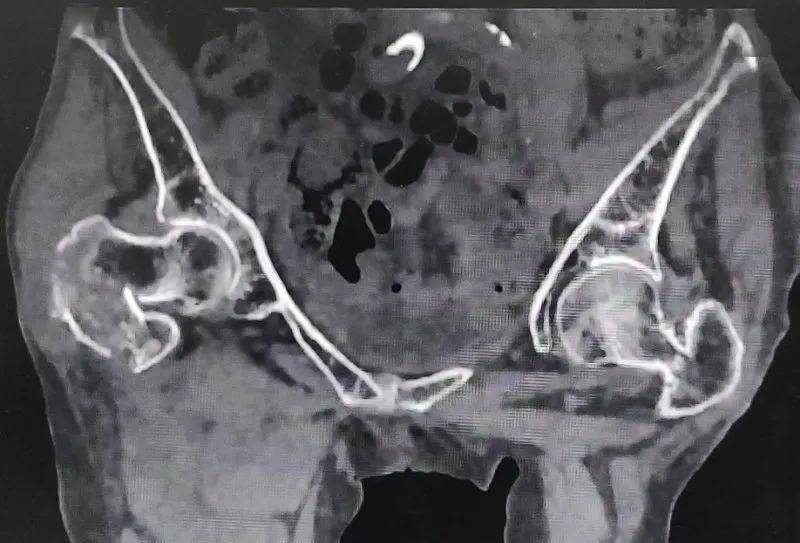

胯骨骨折x光片图片

胯骨骨折x光片图片,骨折x光片图片

x线及ct示:右耻骨下支骨折,右骶髂关节骨折.